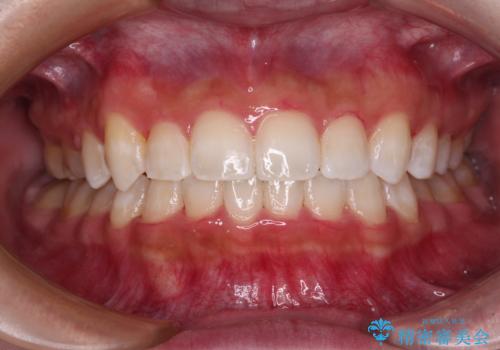

八重歯を改善 目立たないワイヤー装置での矯正治療

前から5番目の乳歯は、後続永久歯である小臼歯と比べて幅径が大きいため、移動に時間がかかりましたが、きれいに仕上げることができました。